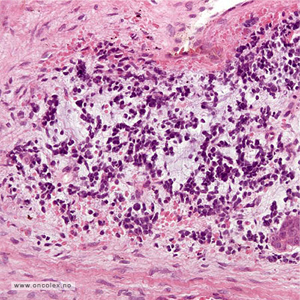

Bildeeksempler:

Kaposis sarkom utgår fra blodårer og som i en tidlig fase mikroskopisk kan ligne på en godartet kartumor (hemangiom). Det er derfor noen ganger nødvendig å ta flere vevsprøver for å finne helt karakteristiske forandringer for denne krefttypen. Mikroskopisk ses spolformete celler og spatier med røde blodlegemer.

Merkelcellekarsinom (nevroendokrint karsinom i hud) utgår fra neuroendokrine celler i hud. Mikroskopisk er dette en småcellet tumor hvor immunhistokjemi ofte brukes for å sikre diagnosen. Finnålspunksjon kan også brukes for å diagnostisere denne tumortypen.